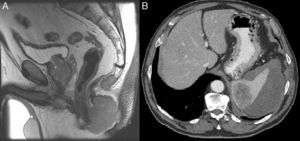

Varón de 66 años, en seguimiento por carcinoma epidermoide de laringe T4N0M0. Presenta tumoración ulcerada a nivel de margen anal izquierdo de 10×5cm de 2 meses de evolución. La resonancia magnética identifica una tumoración perianal con posible infiltración de músculo puborrectal e implante metastásico a nivel de coxis (fig. 1A). Mediante tomografía computarizada se aprecian múltiples adenopatías inguinofemorales y mesentéricas, con metástasis a nivel del riñón izquierdo y en el bazo. Esta última alcanza los 6cm y condiciona un hematoma subcapsular contenido (fig. 1B). La biopsia anal muestra carcinoma epidermoide de canal anal.